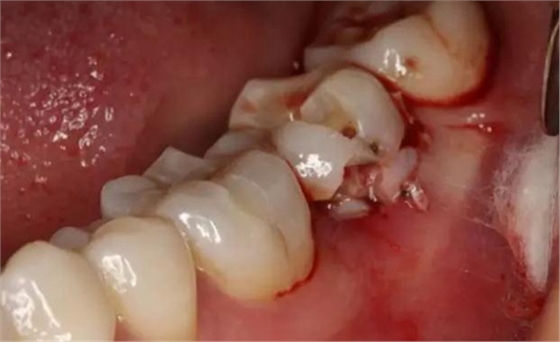

圖6.微創(chuàng)挺拔除37。

圖7. 37牙冠碎裂。多生牙壓迫吸收程度嚴重。

圖8.拔除的37頰側(cè)的牙根完全被壓迫吸收完。